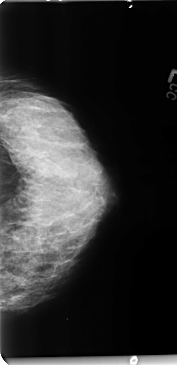

B_3127_1.LEFT_CC

LEFT_CC LINES 4744 PIXELS_PER_LINE 2296 BITS_PER_PIXEL 12 RESOLUTION 50 NON_OVERLAY